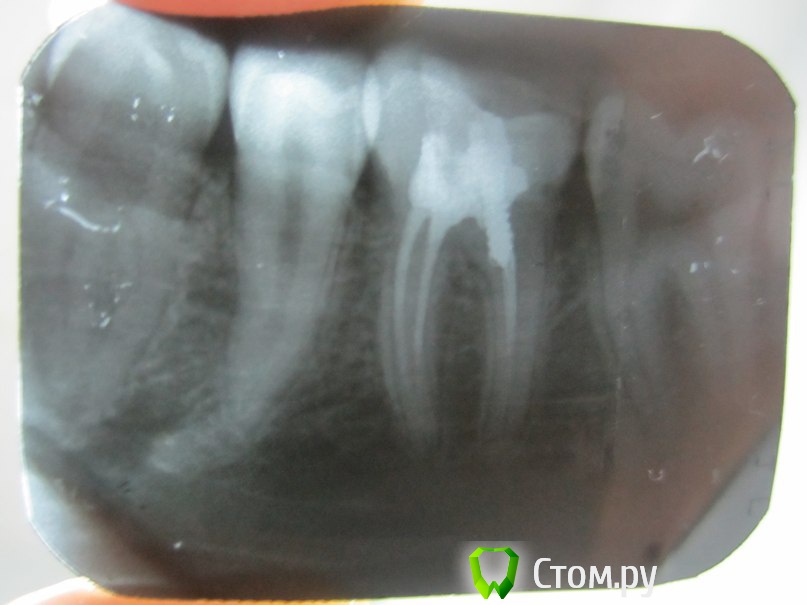

lainux Опубликовано 29 ноября, 2014 Поделиться Опубликовано 29 ноября, 2014 (изменено) Уважаемые врачи, добрый вечер. Два месяца назад установили штифт, зуб периодически стал беспокоит, чувствуется при постукивании по нему небольшая боль. Пошёл к врачу которая делала со снимком, платный кабинет, переделывать отказалась, что её ошибки нет и каналы запломбированы хорошо, сказала попить антибиотики, что продлит неудаление зуба, расстроился нереально. По пути проконсультировался в другой стоматологии, сказали что не долечен канал со штифтом который и надо переделывать, но никак не удалять. Прошу помочь и проконсультировать как быть Изменено 29 ноября, 2014 пользователем lainux Ссылка на комментарий

Shaid Опубликовано 30 ноября, 2014 Поделиться Опубликовано 30 ноября, 2014 Зуб перелечивать(желательно у эндодонтиста). Ссылка на комментарий

Бобр Опубликовано 30 ноября, 2014 Поделиться Опубликовано 30 ноября, 2014 Зуб перелечивать и далее ортопедическое восстановление коронки зуба. Антибиотики этот зуб не вылечат, это точно Ссылка на комментарий

red_butler Опубликовано 30 ноября, 2014 Поделиться Опубликовано 30 ноября, 2014 то есть который стоматолог делал, тот и должен переделывать?Это Вы решайте сами. Если хотите сохранить зуб, нужен специалист владеющий современными протоколами эндодонтического лечения, работающий с коффердамом и в идеале микроскопом, и после лечения зуб протезировать. Ссылка на комментарий

Shaid Опубликовано 3 декабря, 2014 Поделиться Опубликовано 3 декабря, 2014 Возможно что техническое оснащение клиники(м.б. бюджетная или эконом-класс), в которой был пролечен зуб, не такое высокое.Зуб лучше перелечить(скорее всего, уже в другом месте). нужен специалист владеющий современными протоколами эндодонтического лечения, работающий с коффердамом и в идеале микроскопом +1 Ссылка на комментарий